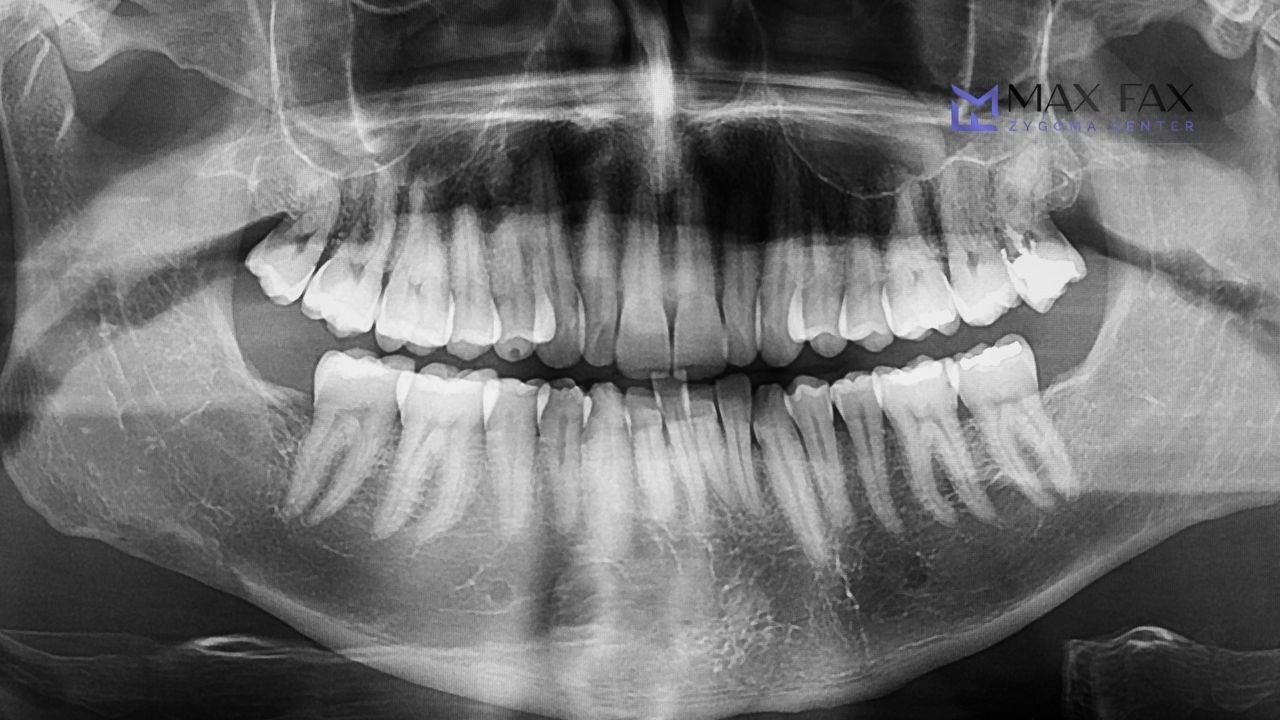

During consultation, it is determined whether the patient is suitable for the procedure. Clinical and radiological examinations are performed, typically including volumetric tomography and panoramic X-rays. The zygomatic arch region is evaluated in detail.

These images allow the surgeon to plan the exact implant placement angle and position with precision, according to the anatomy of the cheekbone as part of the Zygomatic Implant Steps.